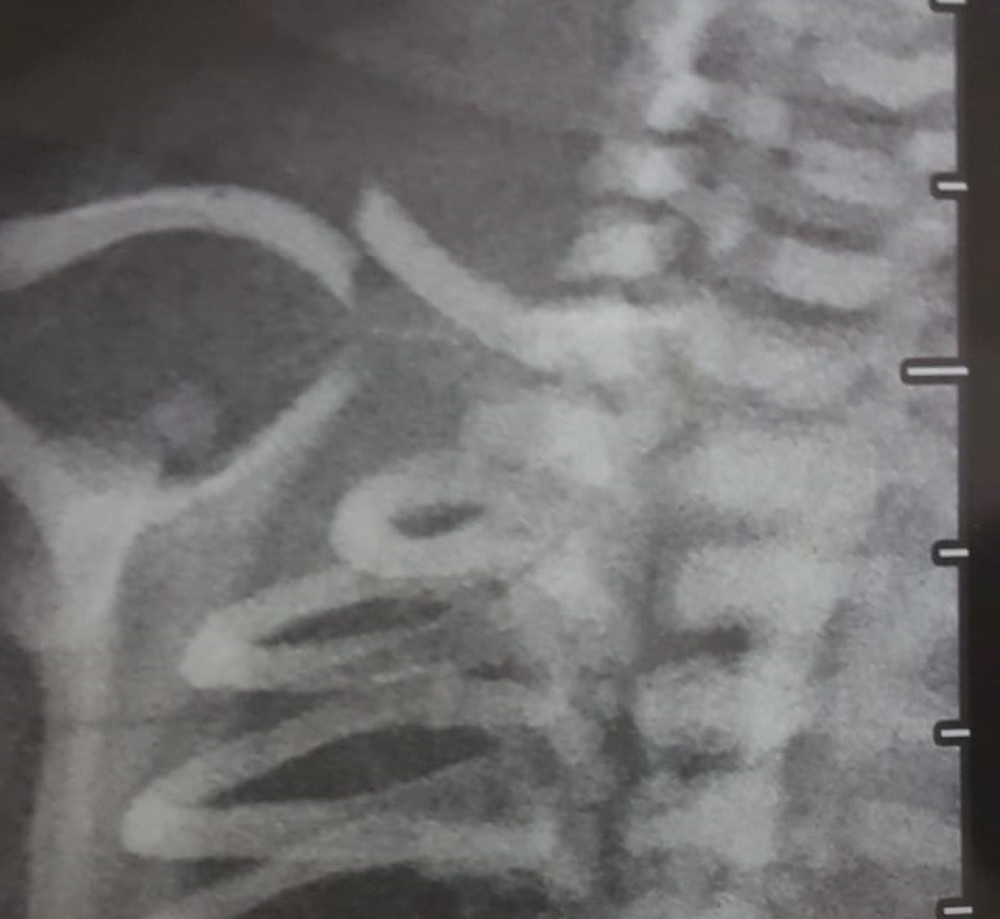

Em um dos casos, uma paciente relatou que um médico quebrou a clavícula de um recém-nascido durante o parto. Apesar do ferimento, a criança sobreviveu. Uma imagem de raio-x, à qual o G1 teve acesso, mostra o osso da criança fraturado (veja acima).